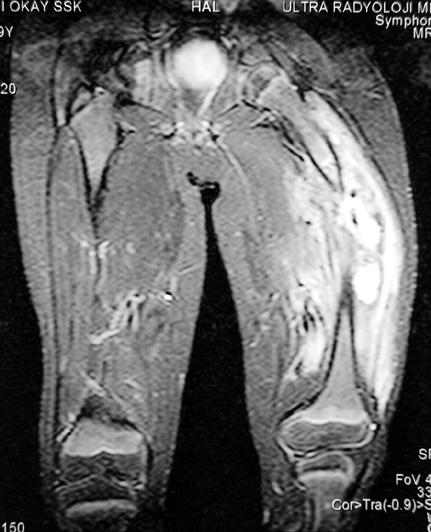

Chronic osteomyelitis leads to necrosis of bone and soft tissues. Dead bone is a nidus which hosts pathogenous microorganisms. Defence mechanisms of the host is usually not in optimum condition to deal with microorganisms. Antibiotics can’t reach the infection site because blood flow is disrupted. For these reasons, dead bone has to be completely removed by radical debridement.

Appropriate radical debridement necessitates excision of all necrotic bone and soft tissues, and frequently causes instability at the involved extremity. The remaining bone and soft tissue defect has to be fixed and reconstructed. The distraction osteogenesis method of Ilizarov is used successfully for achievement of union, correction of the deformity, elimination of limb length inequality and reconstruction of segmental bone defects.